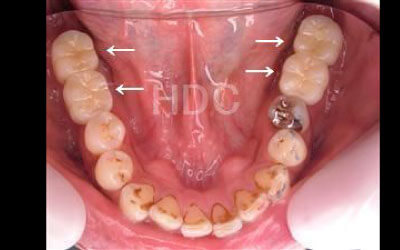

お口の状態や噛み合わせによるので一概には言えないですが、基本的には奥歯がお勧めです。

特に大臼歯と言われる一番奥と奥から二番目の歯の部分です。

噛み合わせの力の60%以上がこの奥から2つの歯で支えているので、ここをしっかりインプラントで治療するのはお勧めです。

2 歯が傾いてくる、落ちてくる

歯の位置は互いに支え合ってバランスを保っています。 つまり、歯が抜けることによって支えが無くなり抜けた部分の両隣の歯が倒れたり、 上の歯が下がってきたりします。